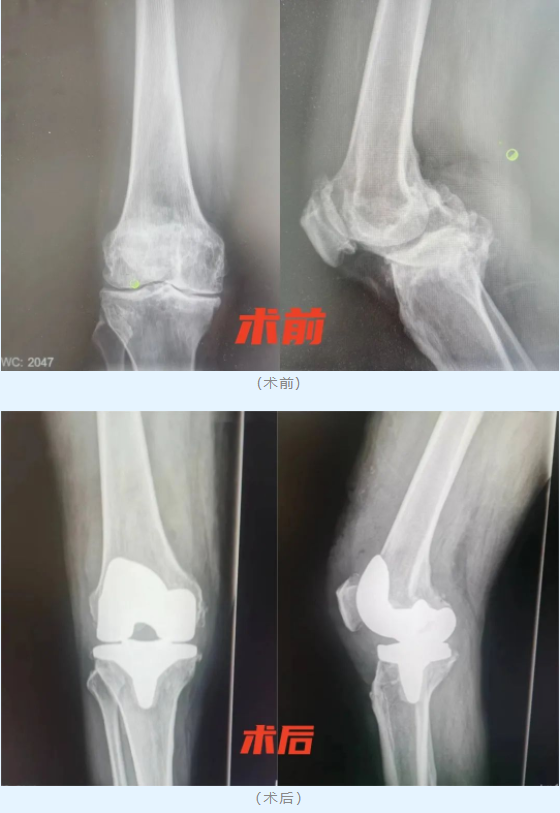

76岁的沈大爷右侧膝关节疼痛多年,天气变化时更严重。今年,膝关节疼痛加剧,平日不能蹲起,连走路都费劲,在家人的带领下,来我院诊治。

我院骨科专家团队接诊后,通过细致的专科检查发现沈大爷患有严重的右膝关节骨性关节炎,查体膝关节屈伸活动明显受限,常规保守治疗已难以达到理想的治疗效果,建议行右膝关节置换术,才能恢复膝关节的功能,解除多年疼痛、行走不便的困扰,提高生活质量。

我院骨科主任杨春生带领的医疗团队,依托精湛的技术和团队的通力合作使本次手术非常顺利,患者术后状态良好,达到预期效果,并指导膝关节功能锻炼,辅助下床活动,膝关节疼痛感明显减轻,目前患者已康复出院。